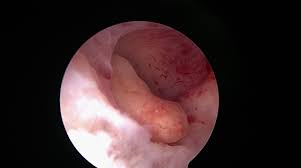

Principalele instrumente de diagnostic pentru evaluarea polipilor endometriali includ ecografia transvaginală, ecografia cu infuzie salină și histeroscopia, aceasta din urmă fiind cea care stabileste cu certitudine diagnosticul. Examinarea ecografică transvaginală poate orienta diagnosticul diferențial cu un nodul fibromatos intracavitar prin utilizarea examinării Doppler, unde în cazul polipilor se poate identifica un singur vas arterial de hrănire.

Polip intrauterin

Tratamentul lor constă în extirparea histeroscopică. Procedurile clasice de îndepărtare prin chiuretaj nu reușesc excizia bazei de implantare, polipul regenerându-se.